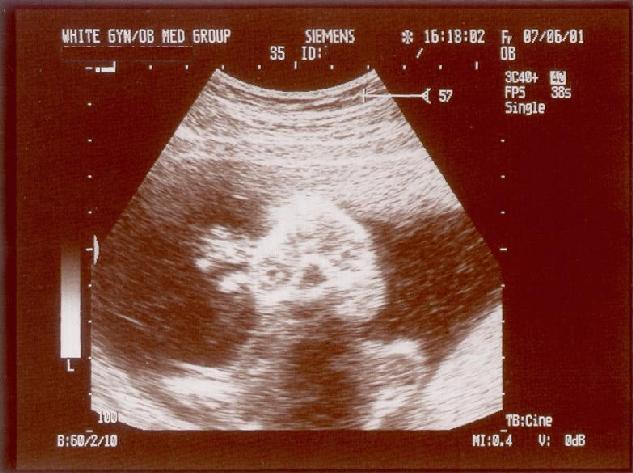

When Liz was about 4.5 months pregnant, the following ultrasound images were taken. They aren't really "Asa"-pictures, as the budding shrimp didn't even have a name yet - as a matter of fact it was only at this Ob/Gyn visit that we learned his sex.

In this image we can see a foot, sticking out upwards. There is a shade of his head visible under the foot in the right lower half of the image.